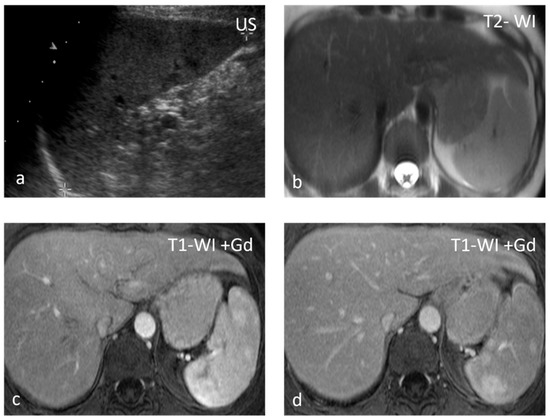

Figure 2.

Sarcoidosis. US shows multiple hypoechoic nodules (a). The nodules appear slightly hypointense on T2 WI (b) and show mild delayed enhancement (c,d).